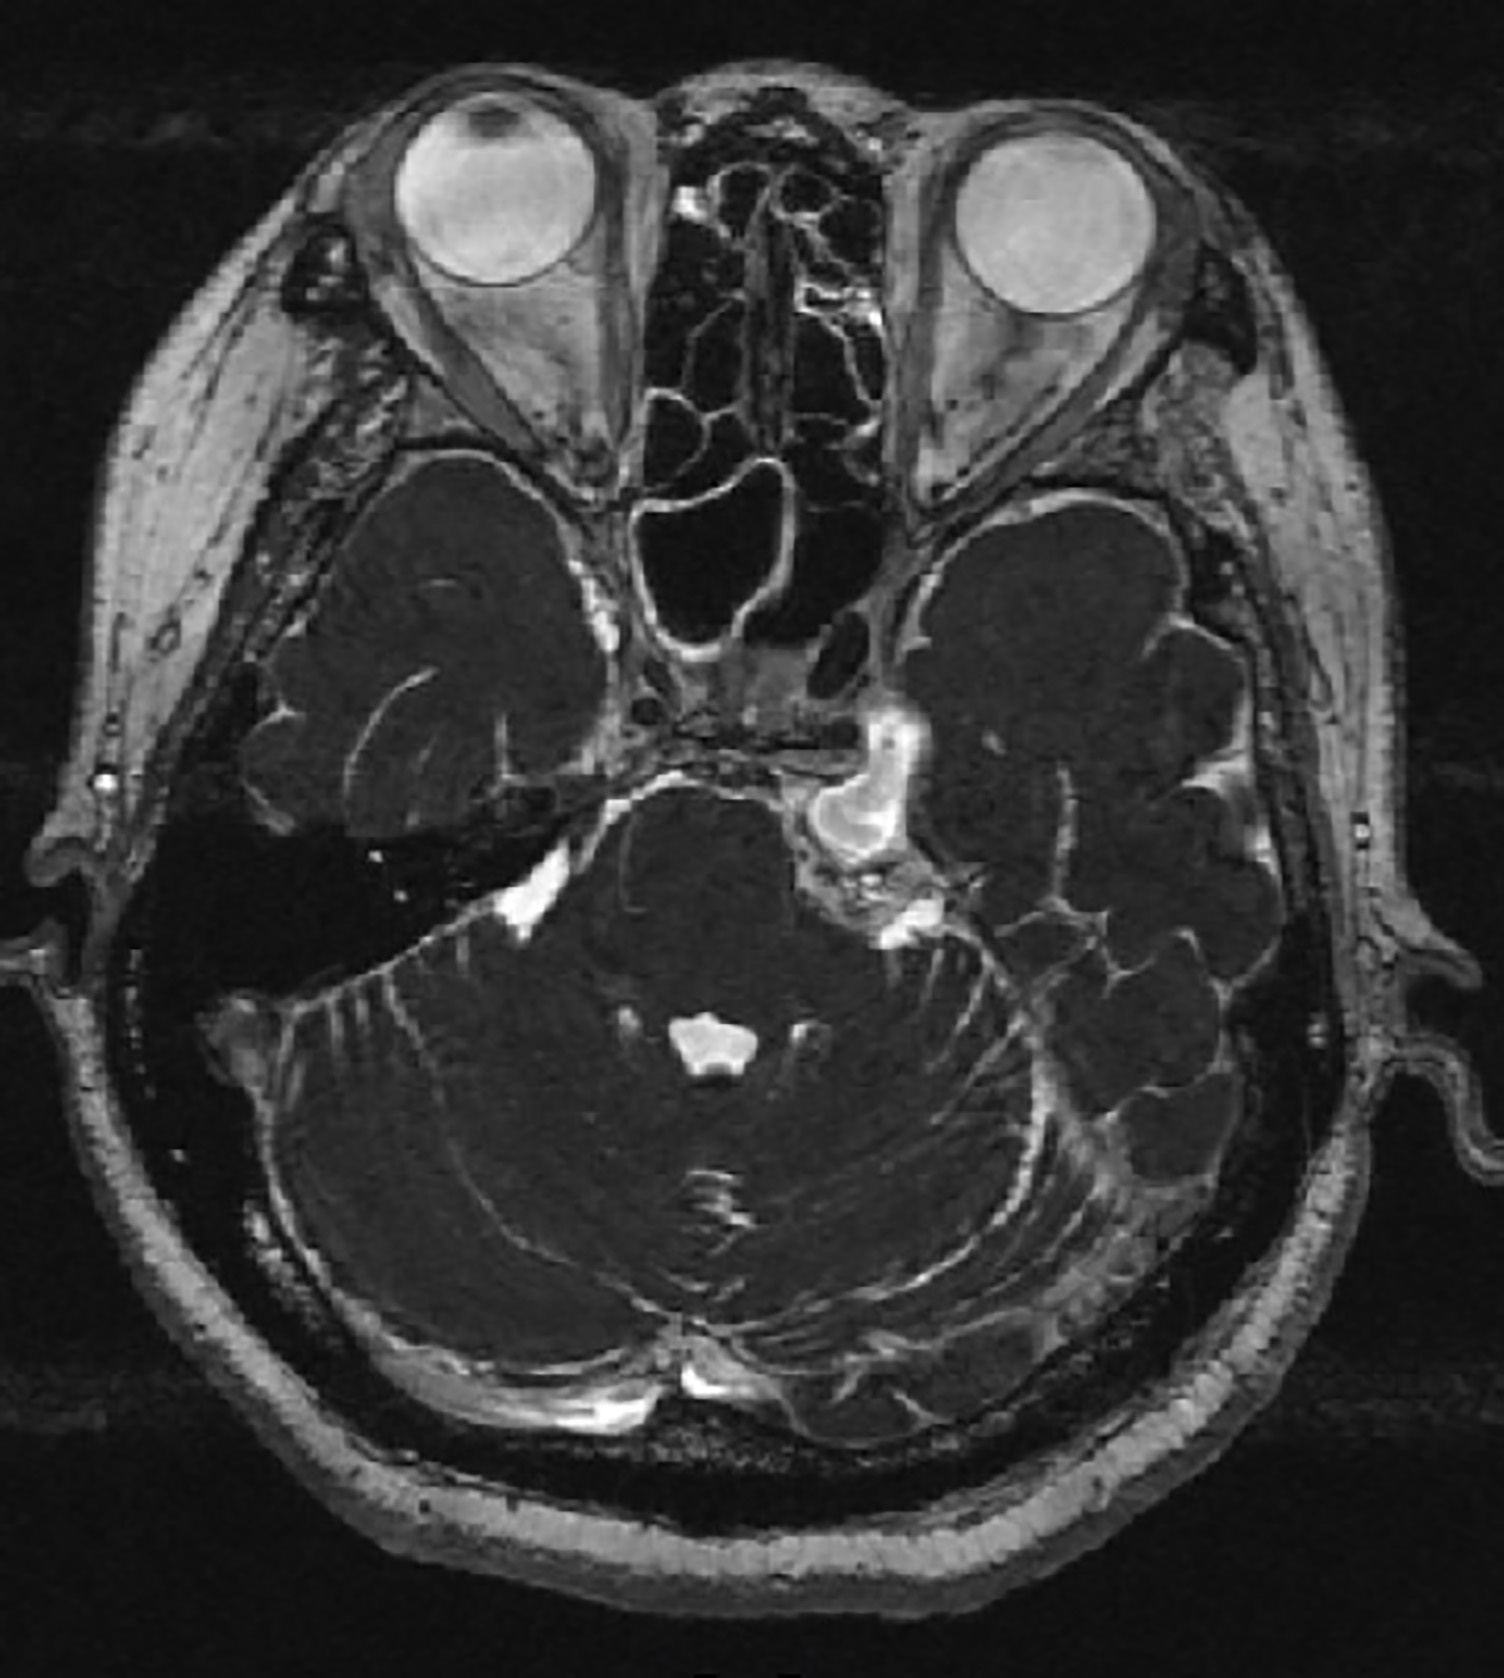

Trigeminal Schwannoma in a Patient with Left-sided Facial Numbness

Cerebellopontine Angle Tumor, Trigeminal Schwannoma, SchwannomaAbstract

We reported a case of an elderly lady who presented with ipsilateral facial numbness and instability for year duration. She was finally diagnosed as having trigeminal schwannoma after seeking multiple medical consultations with her doctors. This case report highlighted a rare cause of cerebellopontine angle tumour that should not be missed given the availability of effective treatment.References